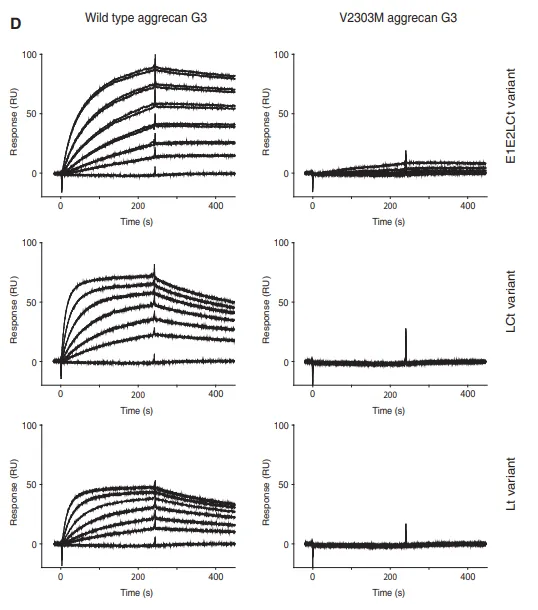

首先,研究人员使用Biacore将细胞外基质纤维蛋白fibulin-2固定在CM5传感芯片上,三种Aggrecan蛋白的野生型与V2303M G3结构域突变体Lt/LCt/E1E2LCt Variant分别作为分析物流经芯片表面,检测不同Aggrecan野生型、突变体和胞外基质蛋白的结合情况。结果如图4所示,所有野生型G3结构域均表现出与fibulin-2非常强的相互作用,而所有V2303M突变体的相互作用则明显减弱甚至丧失。

图4 不同G3结构域野生型、突变体和胞外基质纤维蛋白的结合情况